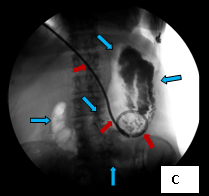

These three images illustrate a variation of how I perform percutaneous gastrostomy. Image A (supine frontal fluoroscope of the upper anterior abdomen) shows gastric insufflation after temporary gastroparesis with intravenous glucagon – distention of the stomach with air (the blue arrows outline the distended stomach) – through a nasogastric tube inserted into the stomach through the nose (the red arrows). The purpose of distending the stomach with air is to bring the anterior wall of the stomach against the anterior abdominal wall, which facilitates passing instruments of the procedure from the outside into the stomach. This is shown in Image B (a cross-table lateral fluoroscope of the upper abdomen) in which the light blue arrows outline part of the air-filled stomach; the purple arrows mark out the skin of the abdomen on which lies a pair of scissors, identifying the skin (the deep blue arrow with red outline); the black thin arrows indicate a 16 gauge needle passing from the surface of the skin into the lumen of the stomach. Image C (also a supine frontal fluoroscope of the abdomen) shows the deployed feeding tube (red arrows) within the stomach (light blue arrows).